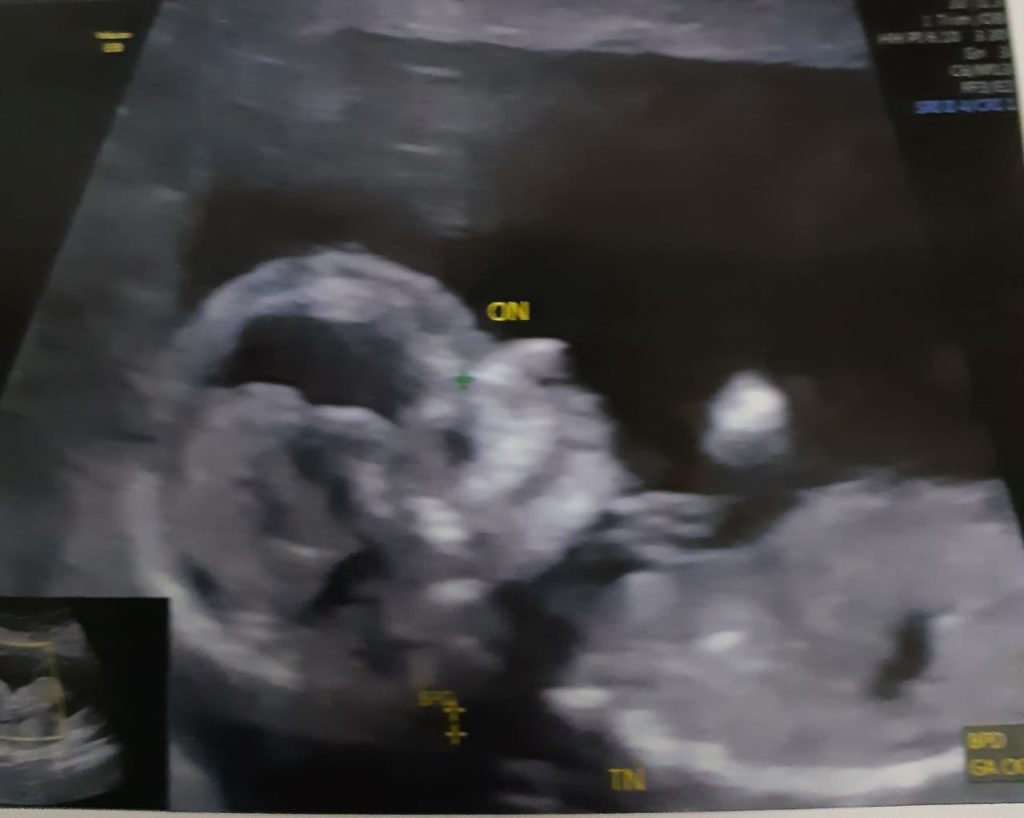

Ao descobrir que mais um bebê estava a caminho em nossas vidas, não imaginávamos passar por um susto. A primeira expectativa é em ver aquele pontinho branco na tela, que pulsa incansável e nos enche de emoção.  Não aconteceu.  A tela ficou preta, eu e meu esposo nos olhamos, sabíamos que não era assim que acontecia, já havíamos passado duas vezes por esse momento… A médica então nos deu a notícia de que talvez o feto não havia fecundado, que podia acontecer. Nos orientou a esperar o corpo expulsar e a conversar com nossa médica.

Passaram-se os dias e finalmente podemos ouvir seu coração bater, lá estava aquele pontinho branco na tela. Estava tudo bem com o bebê.  E as lágrimas foram de felicidade desta vez.

E cá estamos, com 14 semanas de muito amor, saúde e felicidade. Agora é esperar para saber se continuarei sendo a única menina da casa ou se terei companhia…